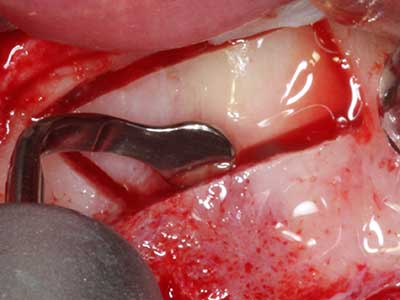

Piezo surgery has additional advantages when harvesting bone blocks. In addition to the high precision with osteotomy described above, the use of the thin saw tips specifically minimizes loss of material. Greater loss of material during harvesting can be expected with the thicker instrument tips, particularly when using Lindemann drills (Lakshmiganthan, Gokulanathan et al. 2012). The basal separation, which is necessary particularly for retromolar block transplants, is simplified by specially designed rectangular saws, with the result that piezo surgery is viewed as a precise, simple and safe procedure for harvesting retromolar bone blocks (Happe 2007) (Fig. 1-12).